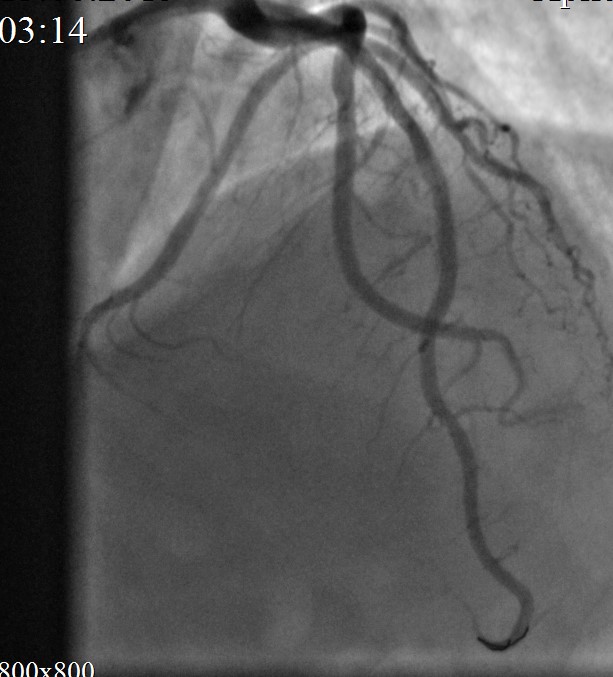

Контрольная КАГ: успешное «пломбирование» разрыва. Кровоток по ПМЖВ TIMI III, в динамике без экстравазации.

Объективно: состояние пациента без ухудшения. Гемодинамика самостоятельная, АД 130/78 мм рт ст PS 80 в мин ЧДД 16 в мин. Жалоб не предъявляет.

ЭХО КС cito: на фоне диффузной гипокинезии миокарда ЛЖ - преимущественная гипокинезия передних сегментов в среднем и апикальном отделах. Глобальные нарушения сократимости ЛЖ (ФВ - 46 %, ФУ - 23 %, диастолическая дисфункция 1 типа). Полость перикарда: расширена спереди до 1,5 см, сзади - до 0,7 см в диастолу (ориентировочное количество жидкости - 250-270,0 мл).